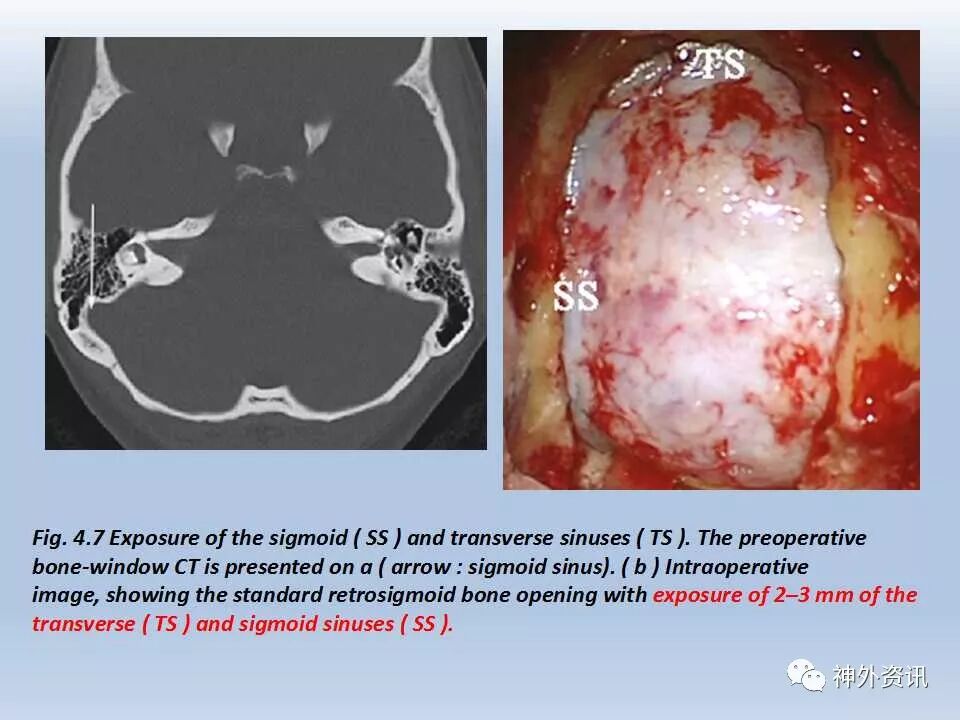

乙状窦后入路经典文献